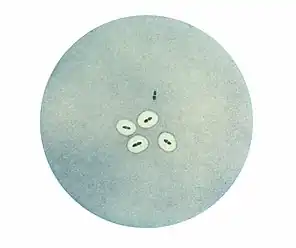

Morphologie

Observé au microscope, le pneumocoque se présente sous forme de diplocoques à Gram positifs lancéolés accolés par leur côté pointu, formant un chiffre 8. Dans les produits pathologiques, les pneumocoques pathogènes sont entourés d'une capsule bien visible[2].

Examen microscopique

La présence de diplocoques capsulés (dans le crachat rouille de la pneumonie lobaire, le liquide cérébrospinal, dans des hémocultures, du pus de sinusite...) permet un diagnostic d'autant plus sûr et précis que les germes sont abondants et constituent l'unique flore observée.